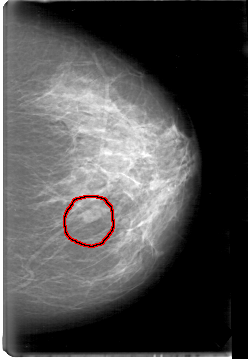

D_4065_1.RIGHT_MLO

FILE: D_4065_1.LEFT_MLO.OVERLAY

TOTAL_ABNORMALITIES 1

ABNORMALITY 1

LESION_TYPE MASS SHAPE OVAL MARGINS OBSCURED

ASSESSMENT 0

SUBTLETY 4

PATHOLOGY BENIGN

TOTAL_OUTLINES 1

BOUNDARY